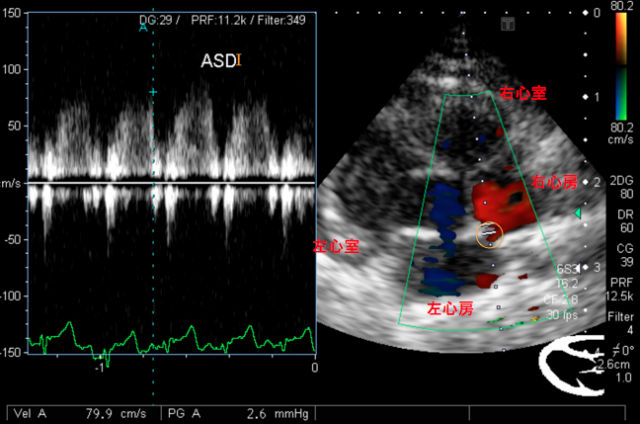

心房中隔欠損

心房中隔欠損は先天的に左心房と右心房の間に欠損孔が生じる病気です。

オレンジの丸の部分に穴が空いています。

多くが無症状で、欠損孔が大きい場合は右心不全を生じることがあります。